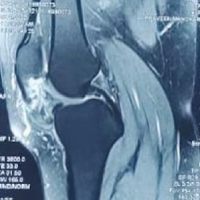

Enchondromas are slow-growing, benign cartilaginous tumors that usually remain asymptomatic and are often discovered incidentally on radiographs. The natural history is generally indolent, although lesions may present with pain, swelling, or pathological fracture. Rarely, malignant transformation into low-grade chondrosarcoma can occur, particularly in syndromic conditions such as Ollier disease and Maffucci syndrome [1,2]. Management depends on symptoms and fracture risk. Small, asymptomatic enchondromas may be observed with serial radiographs [3]. Symptomatic lesions or those complicated by fracture are typically treated surgically with intralesional curettage. Options for filling the defect after curettage include autologous cancellous bone graft, allograft, synthetic substitutes, or bone cement [3,4]. Some studies suggest that leaving the void unfilled may yield equivalent results [4], while others recommend grafting to enhance consolidation and reduce fracture risk [3,5]. Prophylactic fixation using K-wires or plates may be required when structural stability is compromised [6]. Overall, the prognosis following adequate curettage is excellent, with high rates of bone healing and functional recovery. Recurrence is uncommon provided that meticulous removal is achieved [1,6].

Enchondroma is the most frequent benign tumor of the hand, accounting for nearly 70% of primary bone tumors in this region [1,2]. The clinical dilemma lies in distinguishing these indolent lesions from low-grade chondrosarcomas, which often share overlapping radiographic features [1]. Surgical management with intralesional curettage remains the standard of care. The role of post-curettage augmentation continues to be debated. Several authors have demonstrated that void augmentation may not be essential, with comparable recurrence and consolidation rates observed even when the defect is left unfilled [3,4]. Others, however, emphasize the benefits of grafting or substitutes to minimize the risk of fracture and hasten incorporation [5,7]. Our results support the use of locally harvested cancellous autograft, which is easily available, cost-effective, and avoids donor site morbidity associated with iliac crest harvesting.